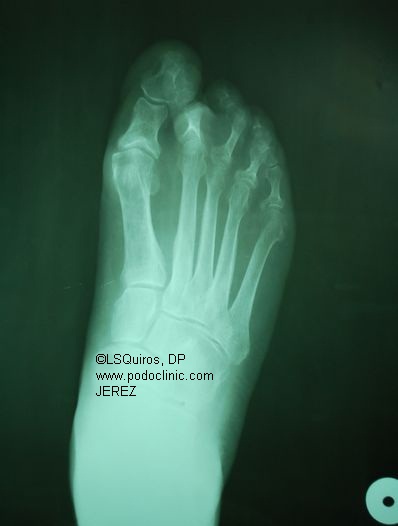

si, pero puse la imagen como para tener noción de lo que significa la inflamación esta. Debe ser bastante molesto y más para un tipo que tiene que entrenar todos los días tener una inflamación así. Me preocuparon mucho sus declaraciones.

El delantero, que padece una bursitis en el dedo gordo del pie derecho, pintó un panorama complicado y crudo con respecto a su lesión y a la posibilidad de poder estar a disposición en el futuro. “El día de mañana quiero jugar a la pelota con mis hijos, no quiero quedar rengo”, disparó. El ‘9’ comentó que agotará todos los medios y, en caso de no mejorar, se operará. Aunque, insistió: “Ya no me importa cuando volveré a jugar”

La cagada de la bursitis en el dedo gordo del pie es que si es jodida te desvia todo el dedo para adentro.

La bursitis es la inflamación de la Bursa (en el dibujo es el “globo” ese azul), que está entre los huesos y los ligamentos.